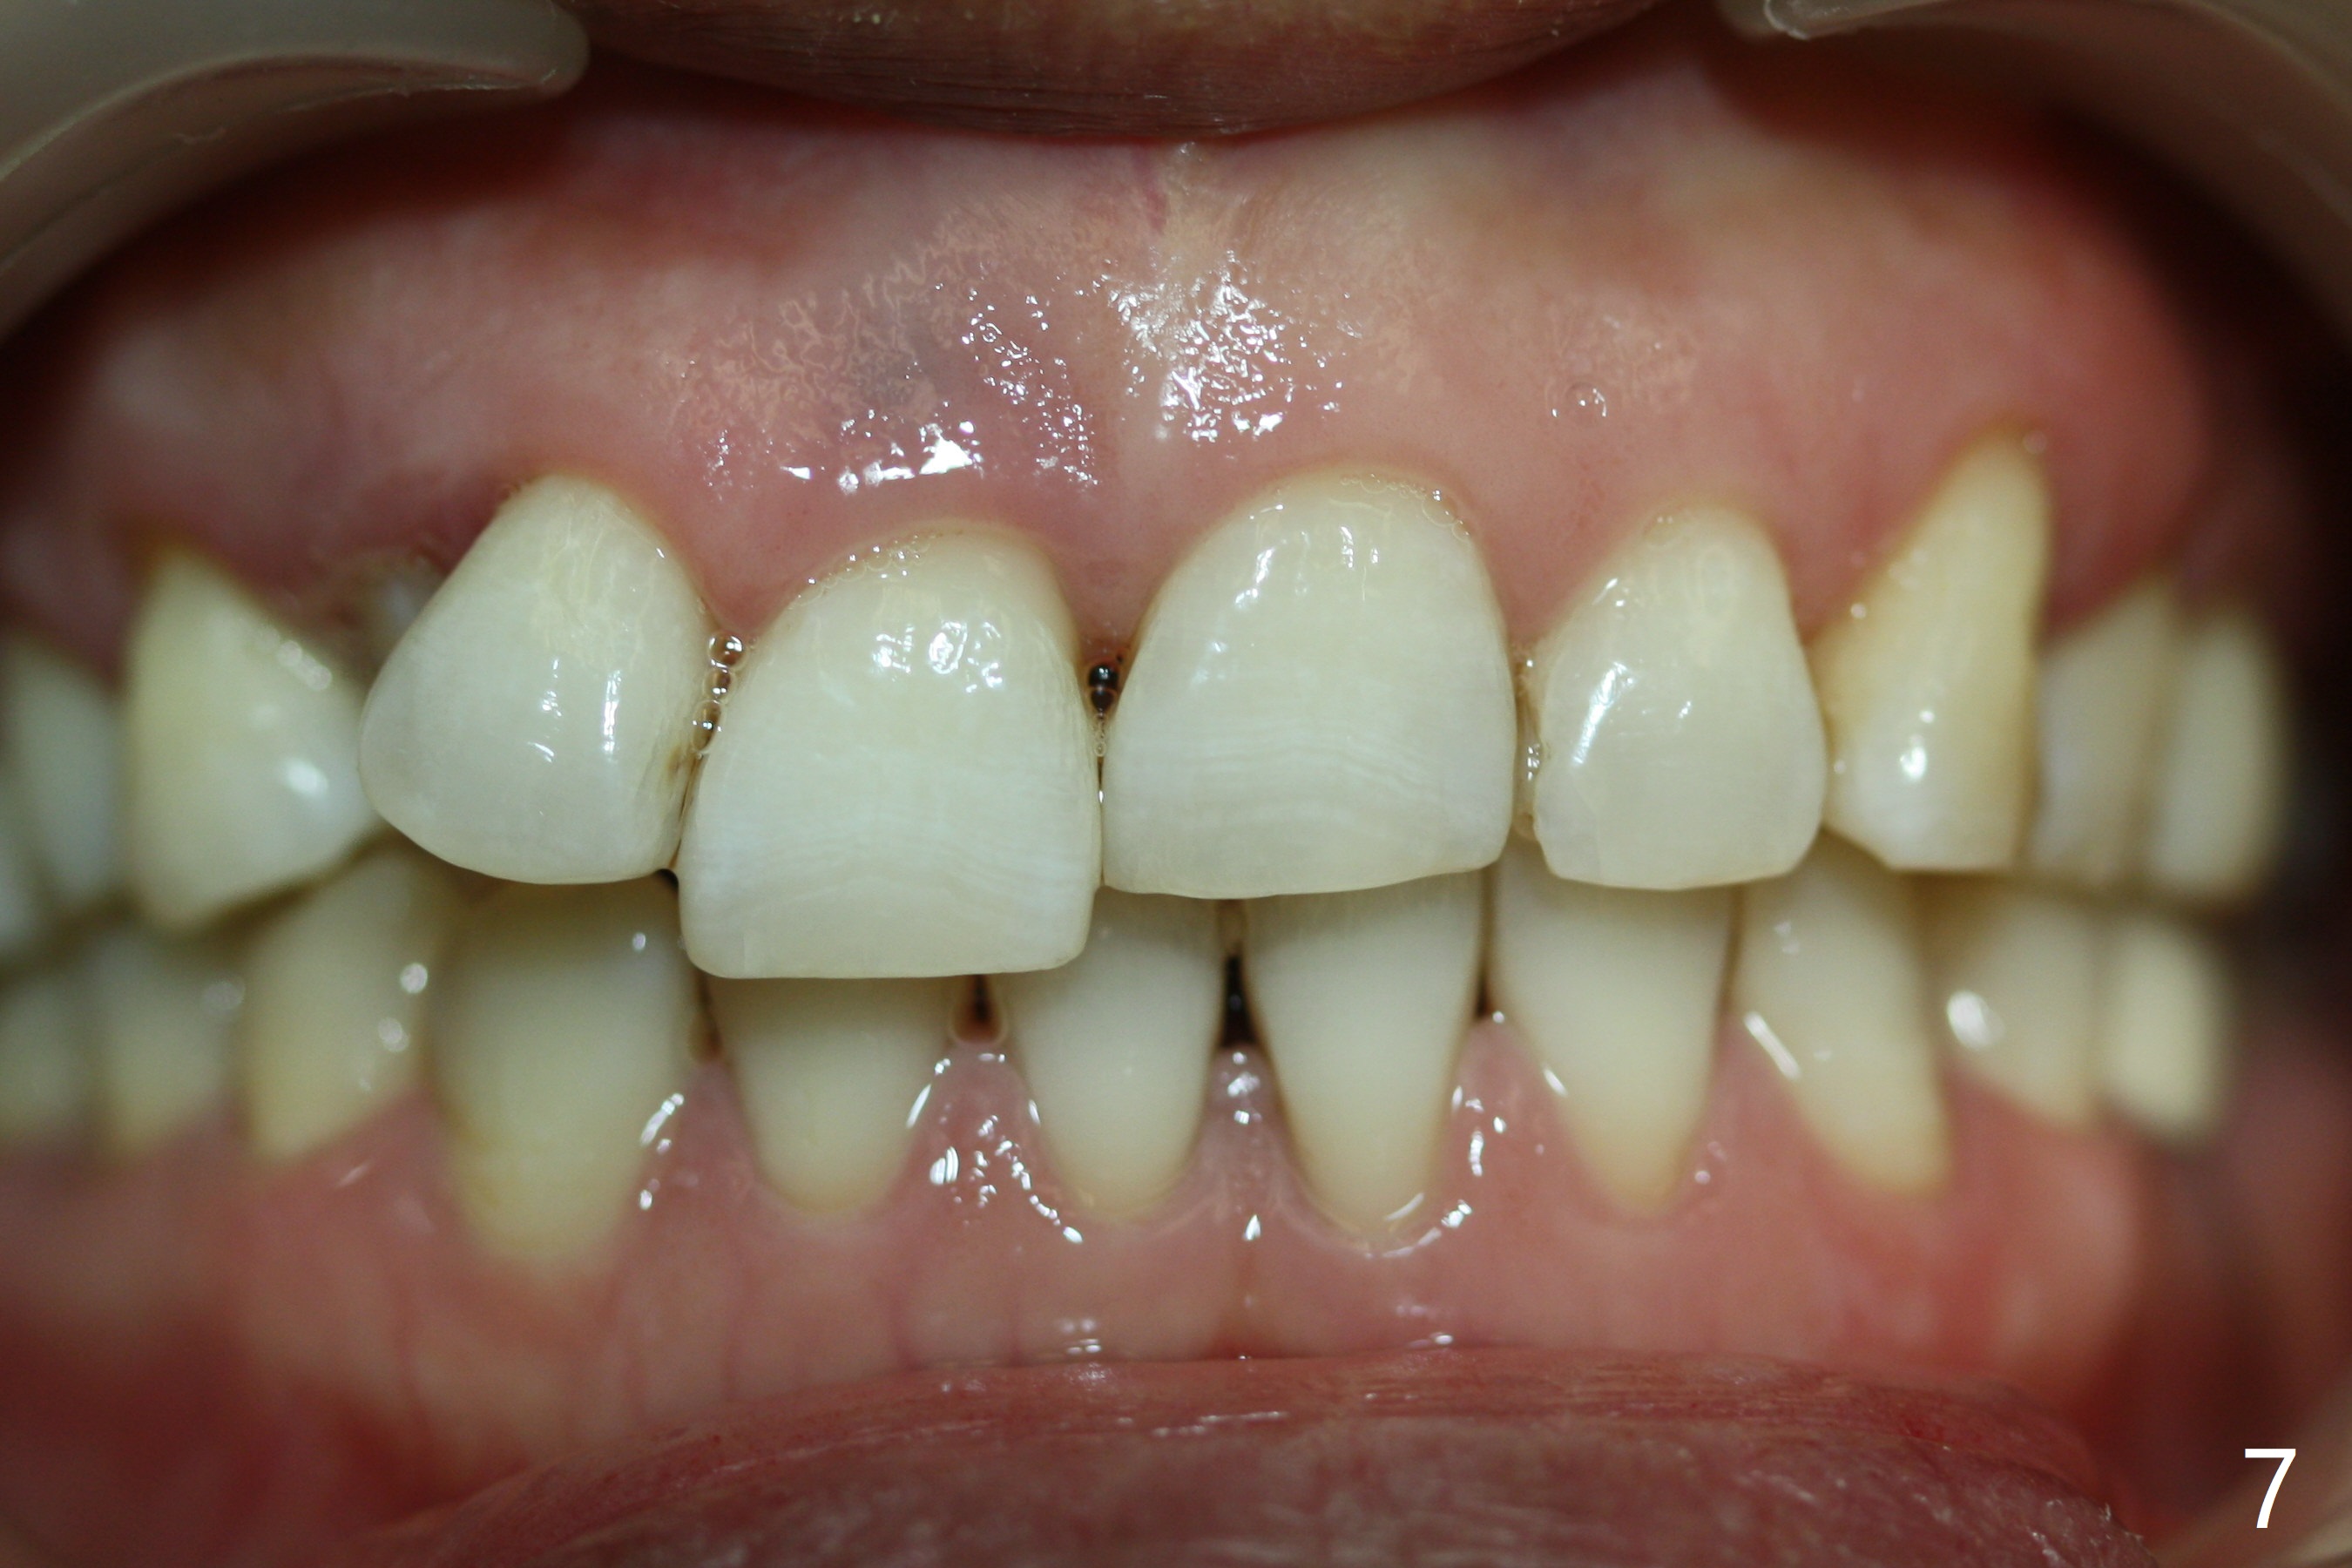

A 48-year-old woman is interested in orthodontic treatment, but is also concerned about whether there will be more loose teeth after treatment (Fig.1-8). The most critical reason for orthodontic treatment is potential recurrent caries in the lingual pit of UR2 and ultimate loss of the tooth if local crowding is resolved (Fig.10).

In addition, the upper dental midline deviates (Fig.2). It appears necessary to extract U4s (Fig.6,8: X) for realignment (Fig.9,11). When UR1 is intruded orthodontically (compare Fig.6,7 with 9) without increased mobility, it will be retained with lingual retainer. Otherwise it will be extracted for implant. Model surgery confirms the necessity of U4 extraction.